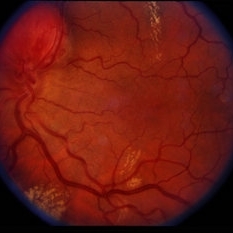

Retinal Capillary Hemangioblastoma

Feb 20 2015 by H. Michael Lambert, MD

No history. Peripheral angioma. Prominent afferent and efferent vessel but it looks to be previously treated and regressed. Over 2 years, no change.

Condition/keywords: retinal capillary hemangioblastoma